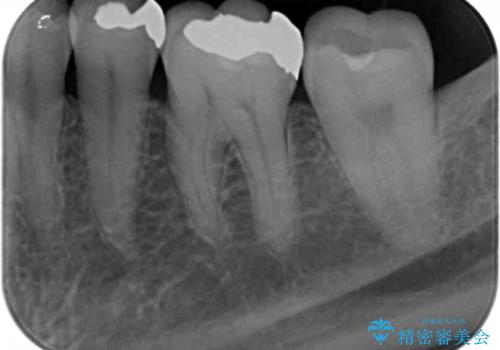

- 長年見た目が気になっていた銀歯のやりかえを希望されて来院されました。

銀歯を丁寧に除去し、セラミクインレーによる置き換えを行いました。

セラミックインレーの治療に際しては、拡大鏡を用いた丁寧な除去・形成、シリコン印象材による精密な型取りを行い、虫歯の再発を防ぐような精密修復を実践していきます。